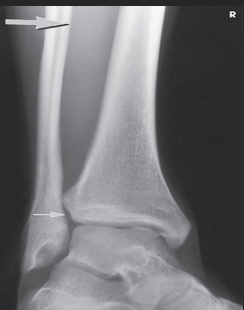

Name this projection.

Lateral calcaneus

What type of projection is it?

Mediolateral

Is the patient on the affected or unaffected side?

Affected

State specifically where the CR enters.

Perpendicular to the calcaneus // 1" distal to the medial malleolus

Which tarsal is in profile?

Calcaneus

Which radiographically significant landmark is open?

Sinus tarsi